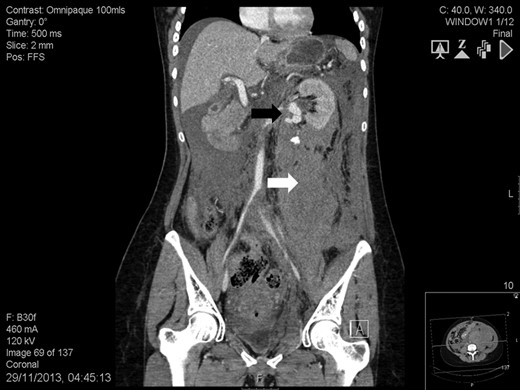

A 41-year-old woman, 21-week pregnant, presented to the Emergency Department with left-flank pain, hypotension (100/60 mmHg) and tachycardia (95 bpm). Blood tests were: haemoglobin 7.3 g/dL, leukocytosis 23.4 cell × 109/L, lactate 3.6 mmol/L, base excess −8.4 mol/L and serum creatinine 82 mmol/L. Abdominal ultrasound was normal but foetal monitoring demonstrated a drop in heart rate suggestive for impending demise. Placental abruption was suspected and following resuscitation she was brought to theatre. We found a large left-sided retroperitoneal haematoma and a non-viable foetus. Exploration also revealed a ruptured left RAA and a contralateral RAA. At this point, it was felt a percutaneous approach would have been more appropriate. Contrast-enhanced computed tomography showed a massive retroperitoneal haematoma, a ruptured left RAA (Fig. 1), and an intact right-sided RAA measuring 2.2 cm (Fig. 2). Under selective angiography, the aneurysm was embolized and the bleeding controlled [3]. Recovery was rapid but a DMSA scan performed 2 weeks later, demonstrated reduced function in the treated kidney (37%). The risk of rupture of the right RAA was deemed significant and a plan for repair was made. The lesion was saccular, wide-necked and located at the artery bifurcation thus preventing endovascular treatment. We opted for hand-assisted retroperitoneoscopic nephrectomy, ex-vivo repair and autotransplant.

Abdomen contrast-enhanced computed tomography scan showing an intact 2.2-cm right renal artery aneurysm (white arrow).